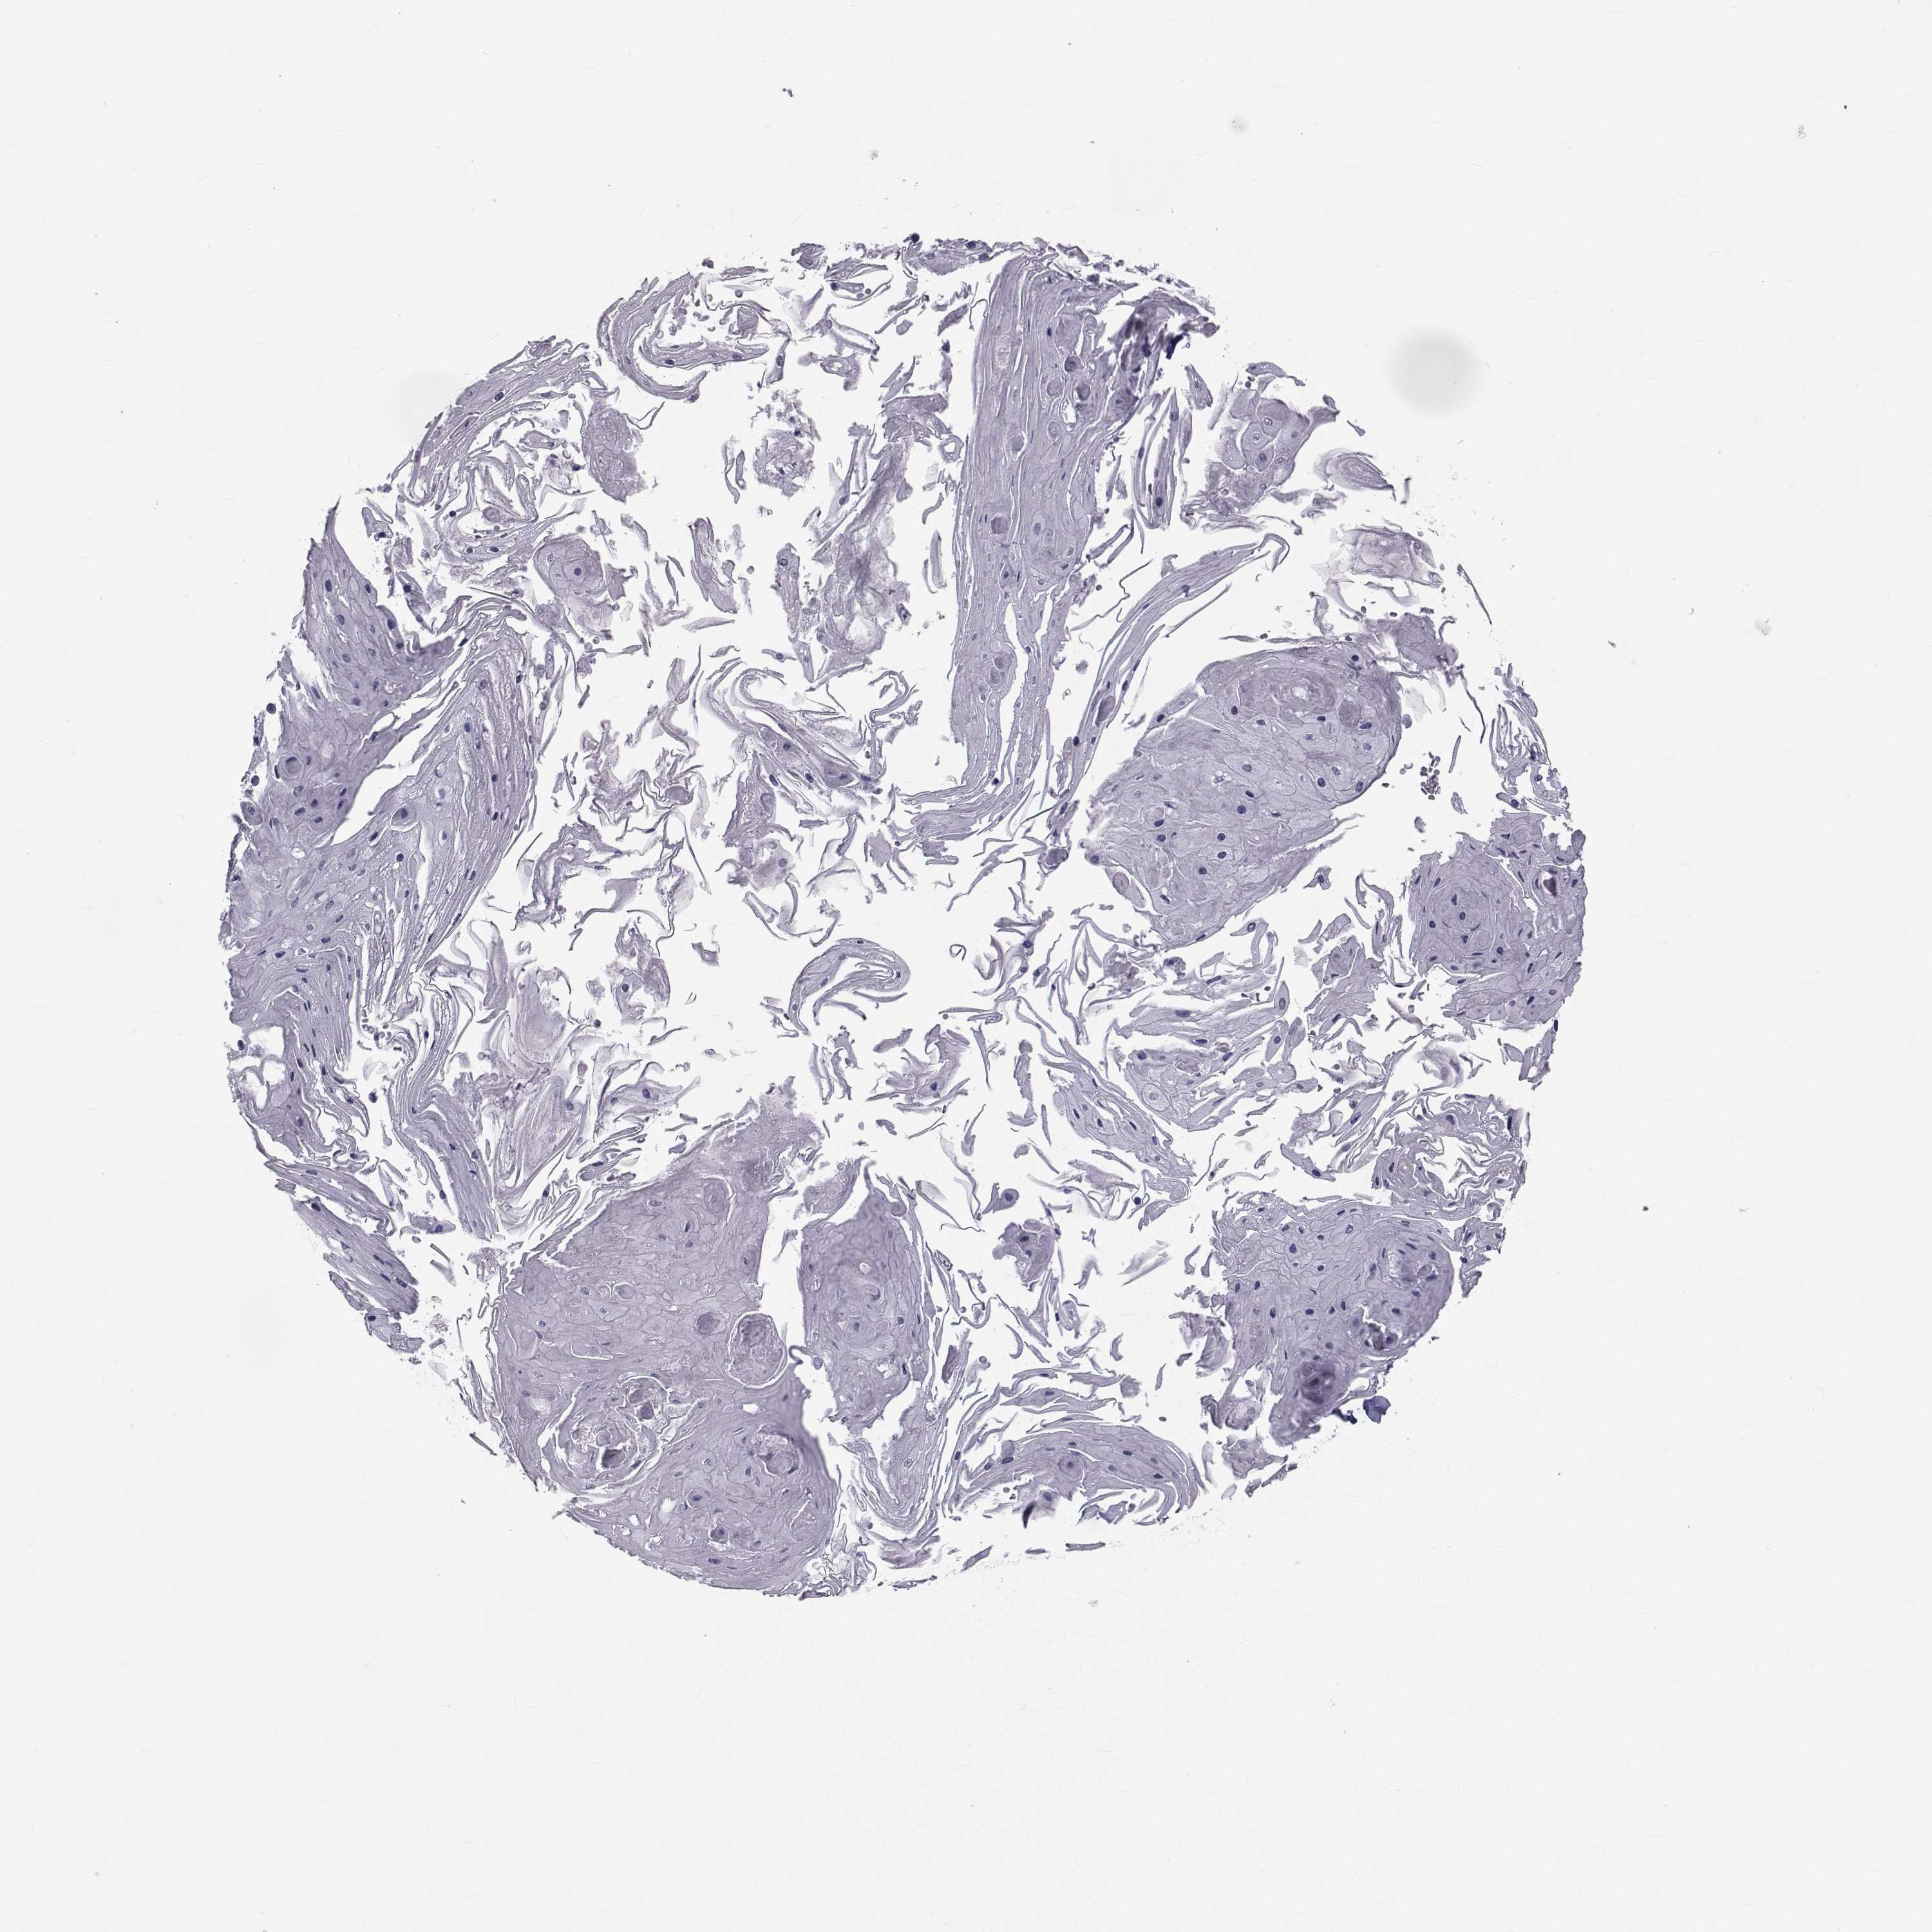

SKIN CANCER - Protein expressioni

A mouse-over function shows sample information and annotation data. Click on an image to view it in a full screen mode. Samples can be filtered based on level of antibody staining by selecting one or several of the following categories: high, medium, low and not detected. The assay and annotation is described here.

Each image is clickable and will lead to virtual microscopy that enables deeper exploration of all samples and also displays staining intensity scores, fraction scores and subcellular localization as well as patient and tissue information for each sample.

Antibody HPA044393

Antibody HPA053673

Antibody CAB009818

Staining

High

Medium

Low

Not detected

Intensity

Strong

Moderate

Weak

Negative

Quantity

>75%

75%-25%

<25%

None

Location

Nuclear

Cytoplasmic/membranous

Cytoplasmic/membranous,nuclear

Squamous cell carcinoma, NOS

Basal cell carcinoma